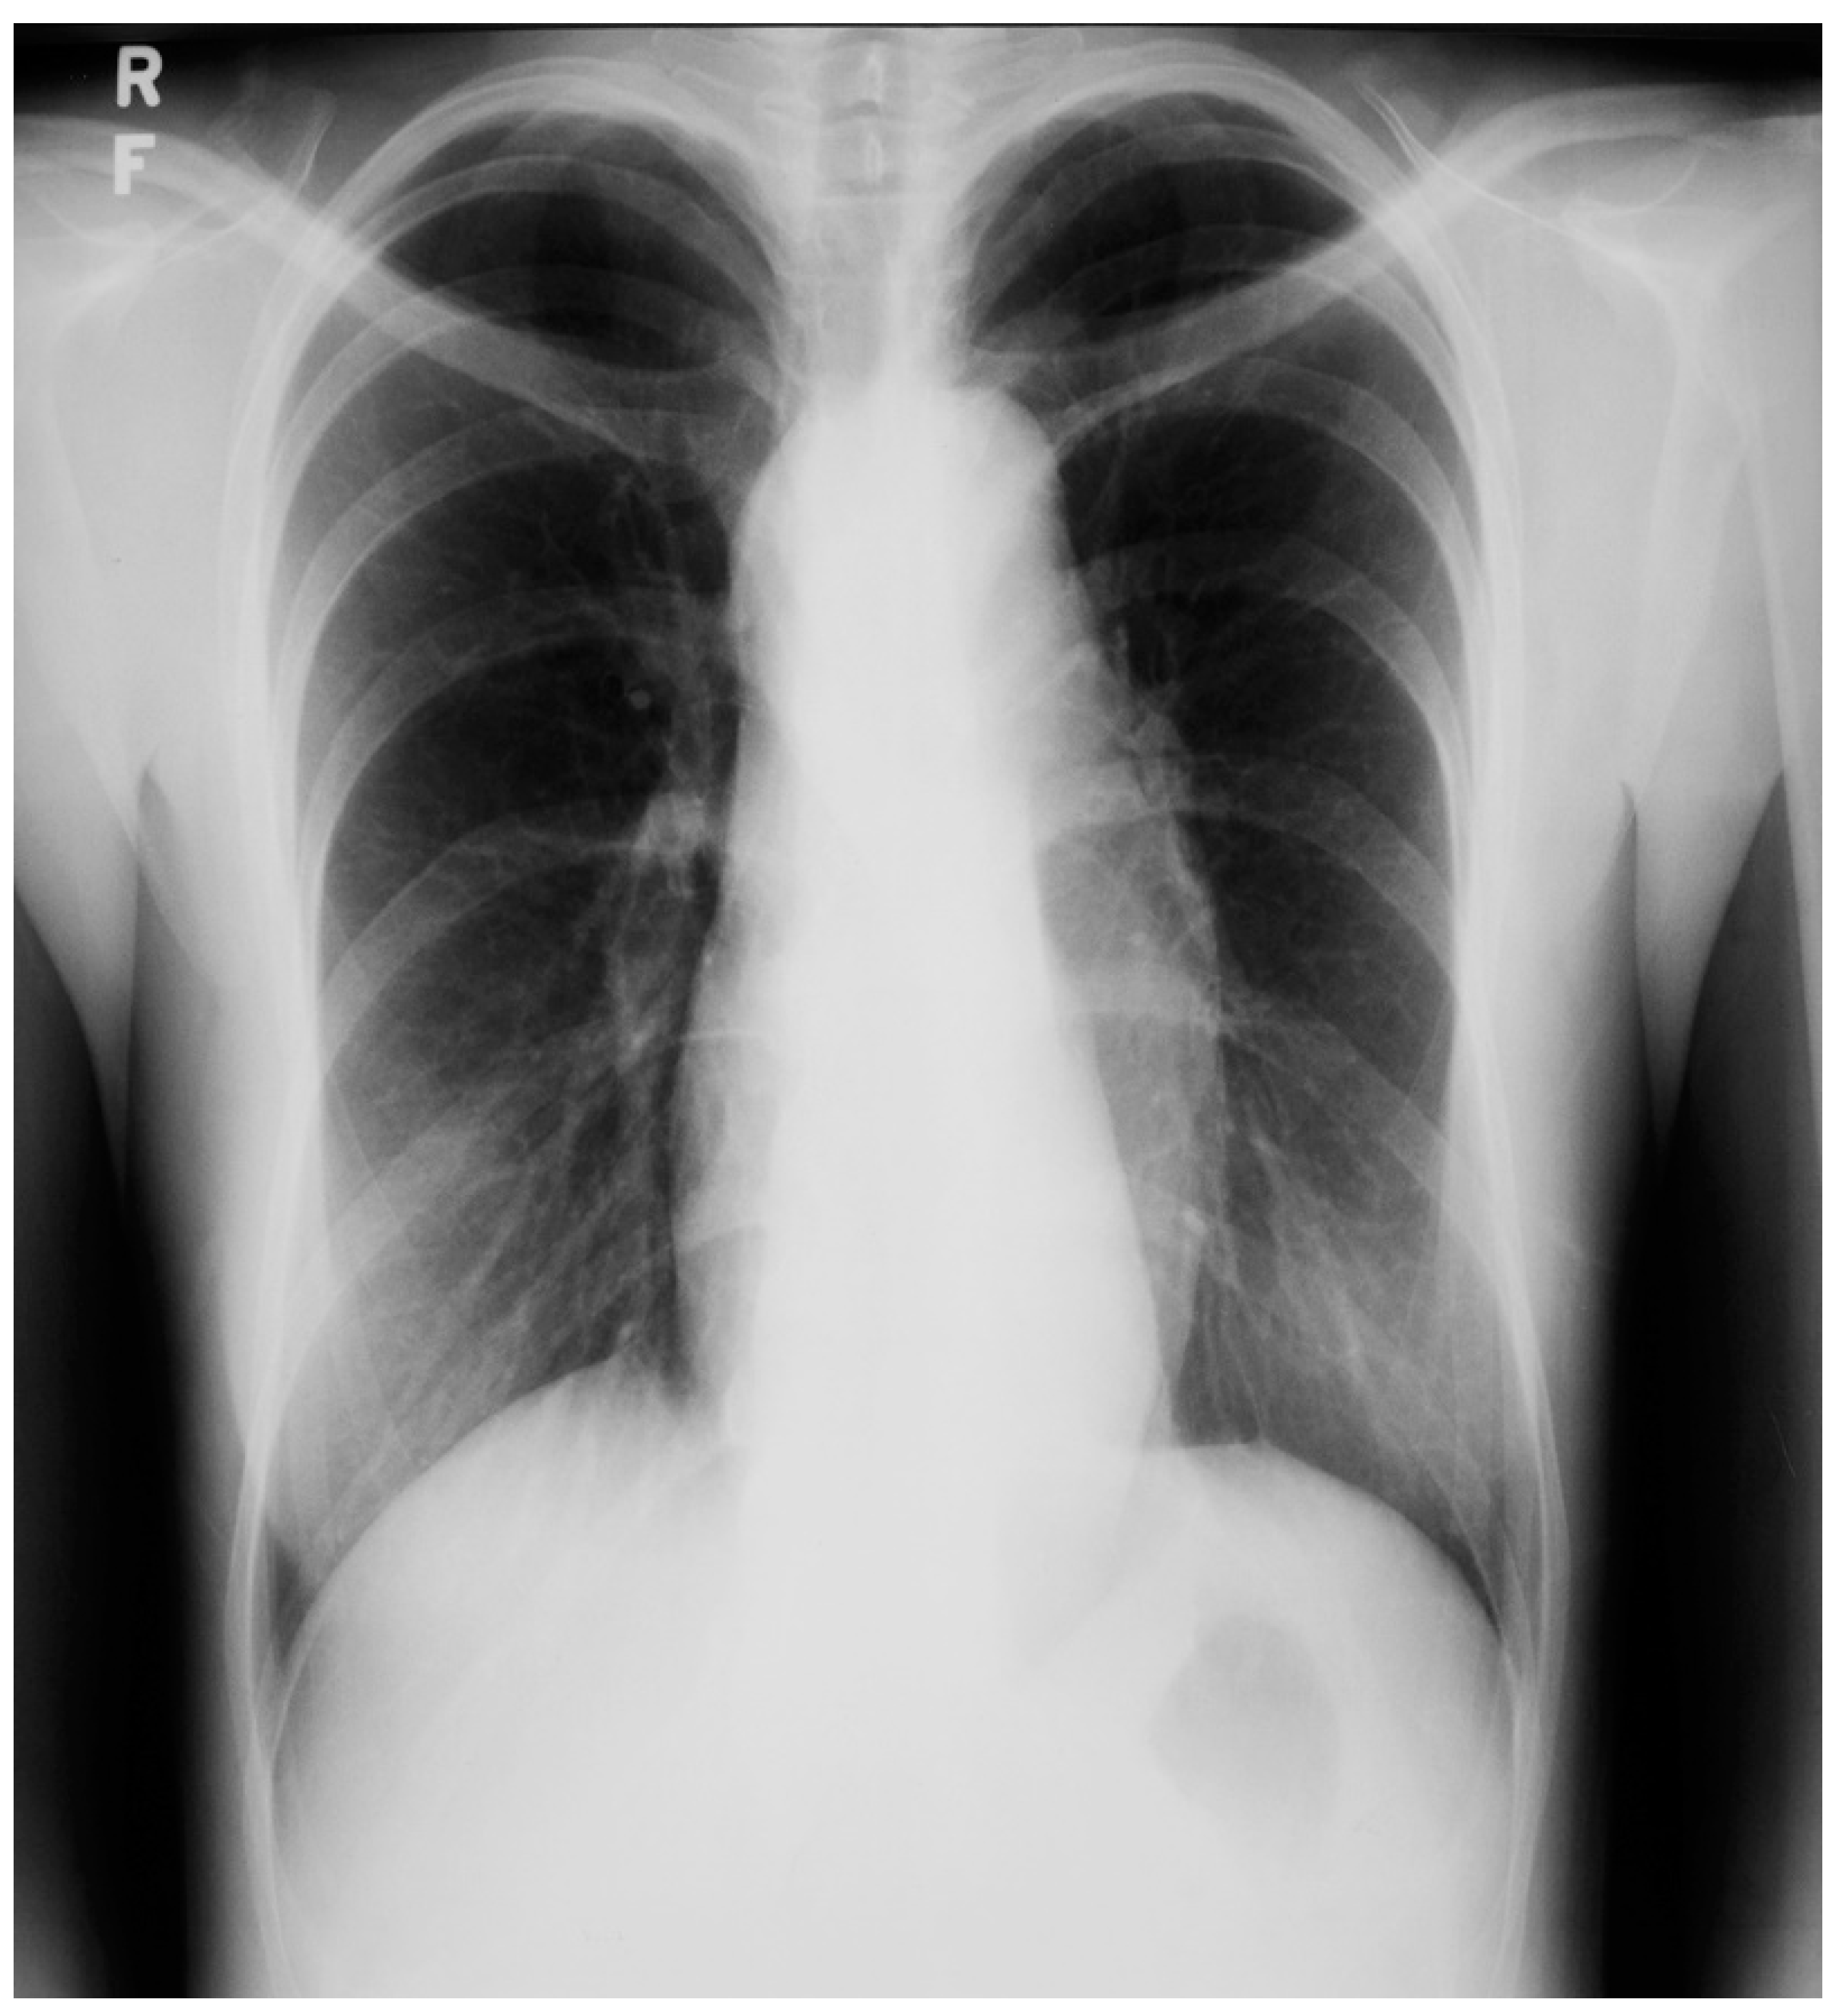

Figure 20.

Posteroanterior chest X-ray of Marfan syndrome: This 24-year-old female with Marfan syndrome had a chest X-ray because of her tall, thin stature and hyperextensible joints. She was asymptomatic. The image is well centered and the inspiration is good. Notice the widened upper posterior dorsal intercostal spaces. This indicates an increased dorsal kyphosis. The C-T ratio is normal. The ascending aorta, aortic arch and descending aorta are dilated. There was a faint decrescendo diastolic murmur of aortic regurgitation at the right upper sternal border. The normal heart size suggests that, in this asymptomatic woman, the aortic regurgitation was mild.